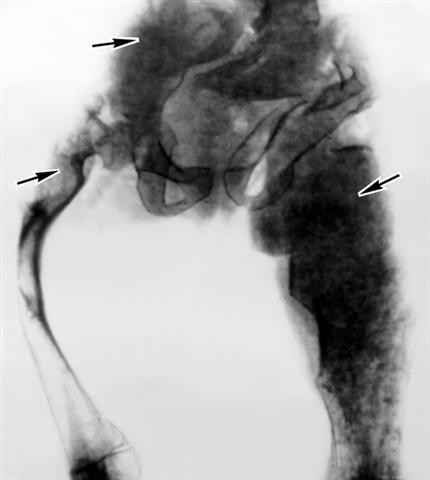

Рис. 2. Рентгенограмма таза и бедренных костей при фиброзно-хрящевой дисплазии: участки кости пятнисто-крапчатой структуры на фоне «матового стекла» (указаны стрелками) и значительное утолщение пораженных костей.